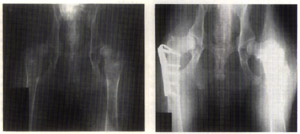

Figure 3 (left) shows before and Figure 4 (right) shows after triple pelvic osteotomy and femoral neck lengthening. Figures 1-4 courtesy of Dr. Barclay Slocum, Slocum Veterinary Clinic.

Note that the intertrochanteric osteotomy and the triple pelvic osteotomy are in essence two approaches to the same overall goal: that of aligning the acetabulum and the femoral head for the greatest congruity. The intertrochanteric osteotomy attacks the problem from the pelvis. If done well, indications are that the results are beneficial and similar. Indications for a triple pelvic osteotomy combined with a femoral neck lengthening are: the dorsal acetabular rim is damaged, the acetabulum is not filled with osteophytes and the joint capsule is stretched. Figure 3 and Figure 4 show before and after imaging of femoral neck lengthening and pelvic osteotomy procedures done on the same animal. Note the great improvement in the femoral head to acetabular cup fit in the after view.